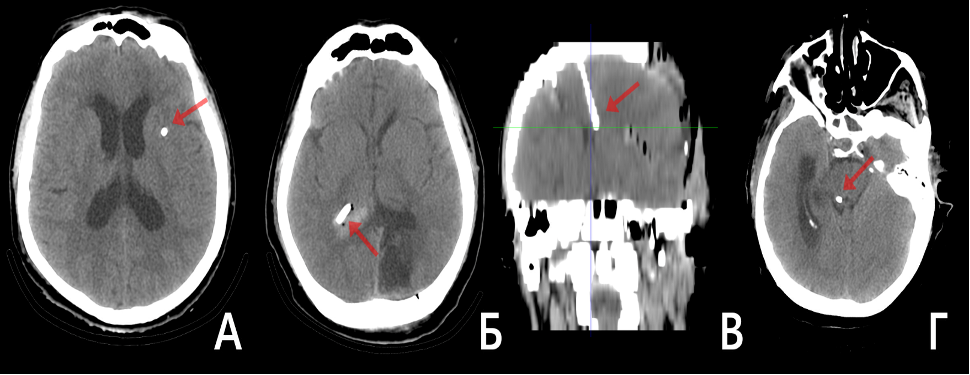

Рисунок 3. КТ томография пациентов с неудовлетворительно установленным НВД (красная стрелка). А – положение катетера в области переднего бедра внутренней капсулы. Б – положение катетера контрлательно в треугольнике правого бокового желудочка. В – контрлатеральное расположение катетера в переднем роге левого бокового желудочка. Г –расположение катетера в области четверохолмной пластинки.